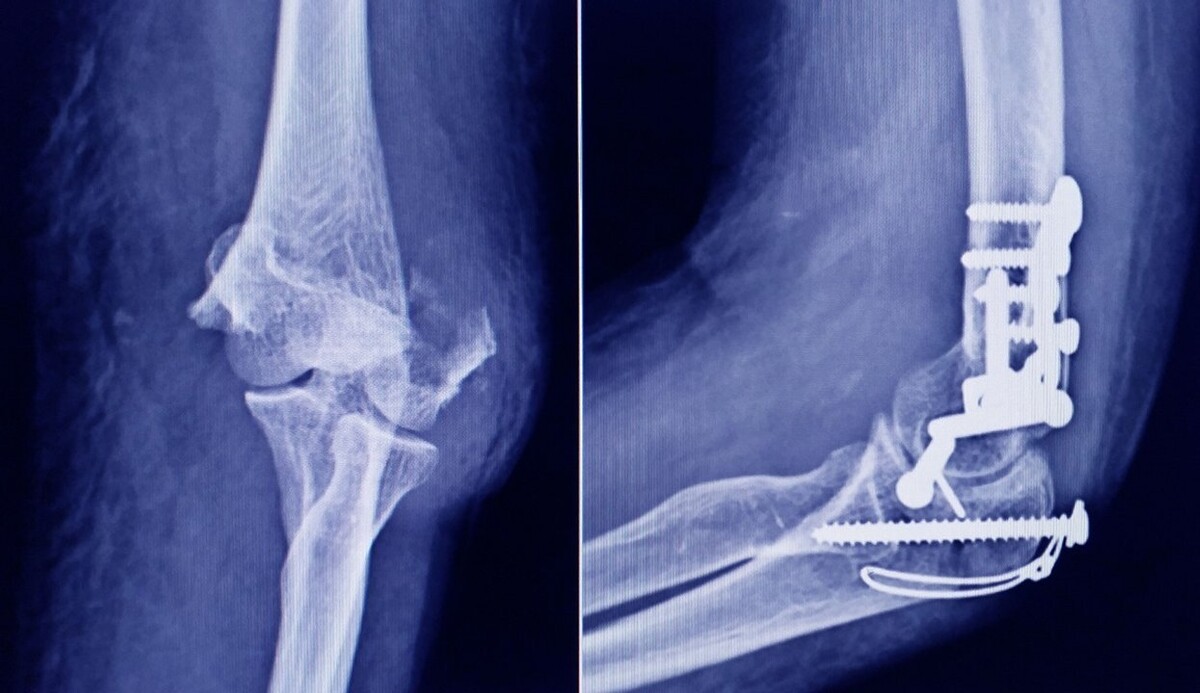

La Administración Nacional de Medicamentos, Alimentos y Tecnología Médica (ANMAT) advirtió a la población por un tornillo utilizado en cirugías traumatológicas debido a que es falso, por lo que su uso representa riesgo para la salud del paciente al que se lo implante.

Se trata de un tornillo utilizado en cirugías traumatológicas que fue detectado durante una inspección de control de mercado realizada en una ortopedia ubicada en la ciudad de San Miguel de Tucumán. Dicho tornillo es producido por la firma Stryker Corporation, que se encuentra registrada ante ANMAT bajo el PM 594-139.

STRYKER 10 mm X 28 mm - BIOABSORBABLE - ACL INTERFERENCE SCREW - REF 234-010-067 - LOT 90905.

La unidad original posee fecha de fin de vigencia mientras que la unidad falsificada no cuenta con este dato. La firma Stryker nunca ha utilizado para este producto pouch marca 3M. El producto original se esteriliza por Radiación Gama, mientras que la unidad falsificada habría sido esterilizada por vapor o formaldehido. El tornillo original es color gris opaco, mientras que el de la unidad falsificada, tal como se observa a través del pouch transparente, es incoloro.